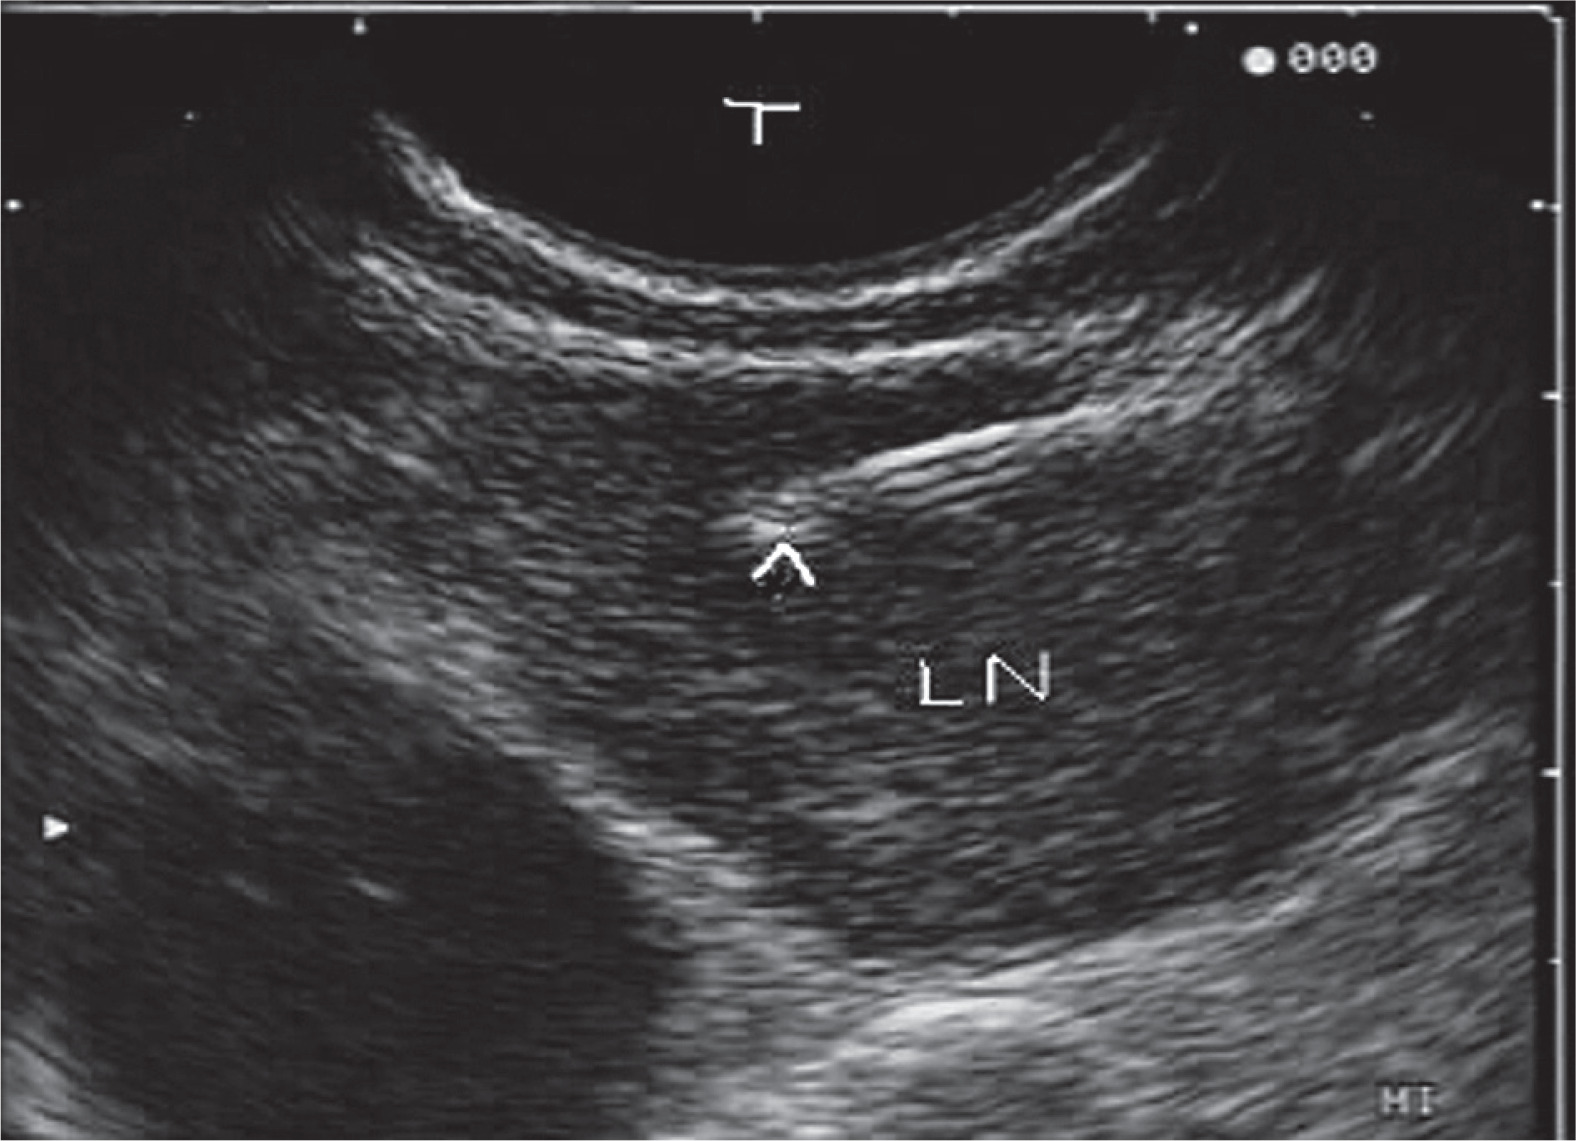

In this era some studies have reported highest applicability in cases using endobronchial ultrasonography (EBUS) with high accuracy in false negative CT scan [11-14]. However, there are some controversies about the role of the EBUS (Figures 1 and 2) versus spiral chest CT scan (Figures 3 and 4) to differentiate between infiltrated and none-infiltrated lymph nodes.